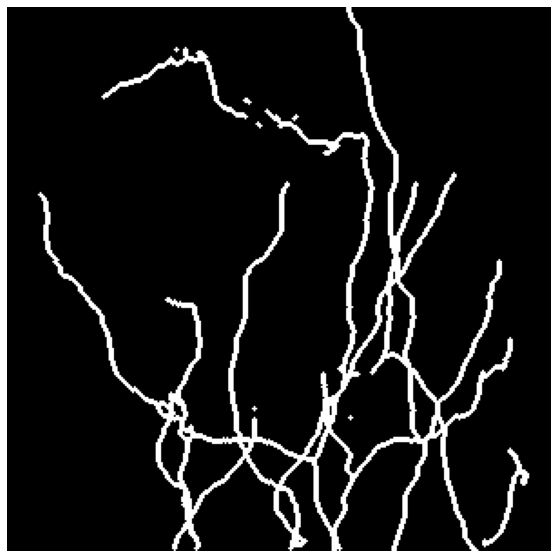

We tested our approach on three data sets. The Brain comprises 14 light microscopy scans of mouse brain, sized . We use 10 of them for training and 4 as a validation test. Neurons contains 13 light microscopy scans of mouse neurons, sized . We use 10 for training and 3 for validation. MRA is a publicly available set of Magnetic Resonance Angiography brain scans [3]. We crop them to size by removing their empty margins, and use 31 annotated scans for training and 11 for validation. A sample image from each data set can be found in Fig. 4.

| Brain | Neurons | Neurons | MRA | |

|---|---|---|---|---|

| Input | ![]() |

![]() |

We provide qualitative results in Fig. 4 and quantitative ones in Table 1. Minimizing our loss function consistently improves the APLS and TLTS by a significant margin compared to minimizing pixel-wise losses. Additionally, our loss outperforms the topology-aware losses Perc and PHomo. It also delivers a boost, albeit only on average, in terms of the CCQ. Box plots in Fig. 3, show that these conclusions hold when variance of the scores is taken into account.

On average, OURS-2D achieves performance that are slightly lower than those of comparable performance to OURS-3D. However, annotating 2D slices instead of 3D stacks significantly reduces the time required to annotate, as shown in the user study conducted in [17]. Thus, when annotation effort is a concern, OURS-2D is an excellent alternative to OURS-3D.